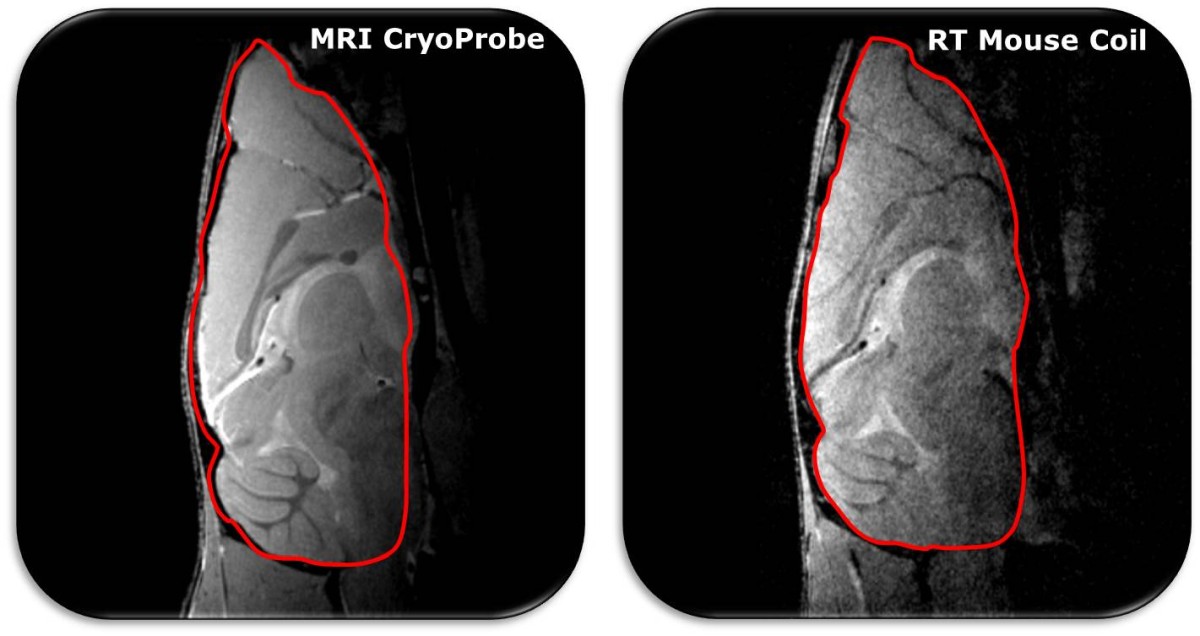

• MRI CryoProbes for SNR boost allowing for up to 6 times faster measurements and/or increased resolution

MRI CryoProbe leads to average SNR increase of factor 2.8 at 9.4 T in mouse brain as opposed to room-temperature mouse brain coil Acquisition details: FLASH, resolution: (78 x 78 x 500) µm³, TR: 400 ms, TE: 3.8 ms, total time: 3 min. 24 s